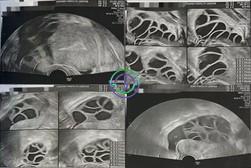

促排第 8 天 — 多个卵泡已逐渐发育,尺寸渐渐增大

超声结果

右侧卵巢:卵泡大小 17,17,17,17,16,12,12,12,11,10,10 mm → 共 11 个卵泡

左侧卵巢:卵泡大小 17,16,16,15,15,14,14,13,12,11,10,10 mm → 共 12 个卵泡